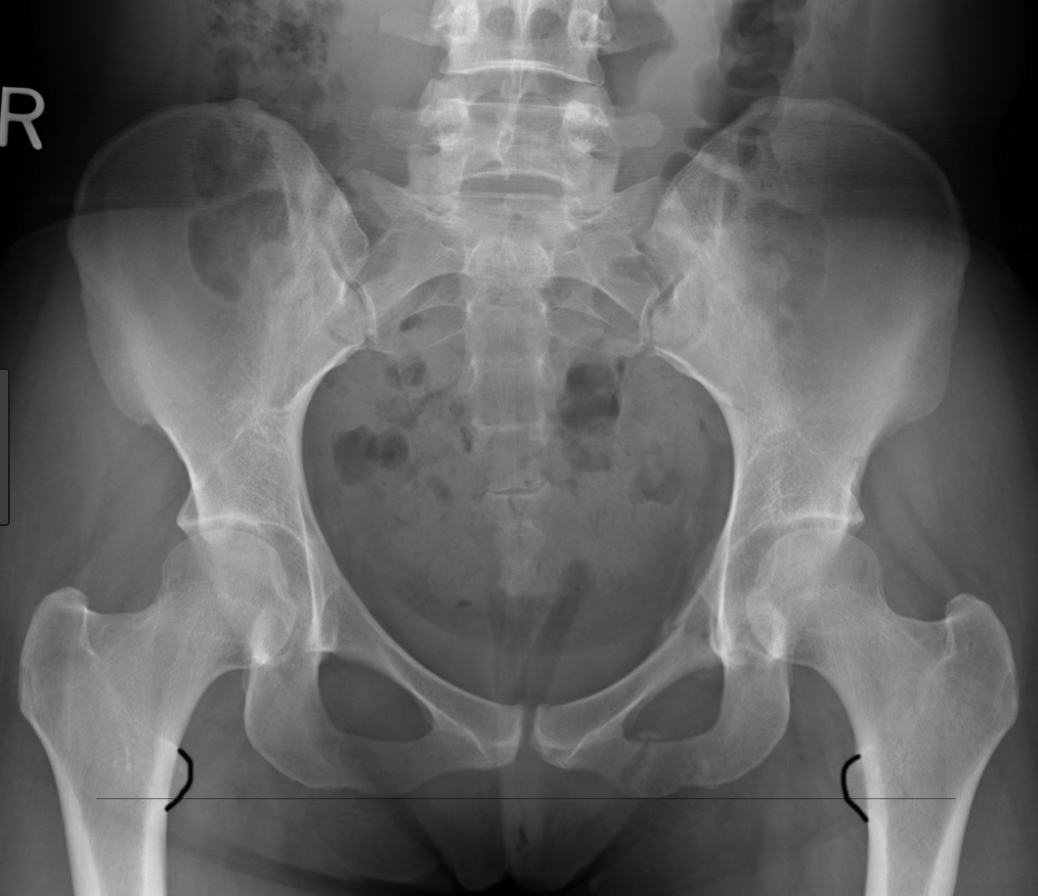

I have a particular interest and decades of experience in total hip and knee joint replacements; as well as revision hip and knee arthroplasty (for worn out total hip and knee replacements).

I manage some sports injuries of the hip and knee and also am heavily involved with pelvic trauma and musculoskeletal tumours and Waikato Hospital..

Total Hip Joint Replacement. A surgical procedure to replace damaged cartilage and bone in the hip joint. Usually, this procedure is performed when pain and other symptopms become severe and significantly interfere with everyday life. Most commonly, the underlying condition is osteoarthritis. More.